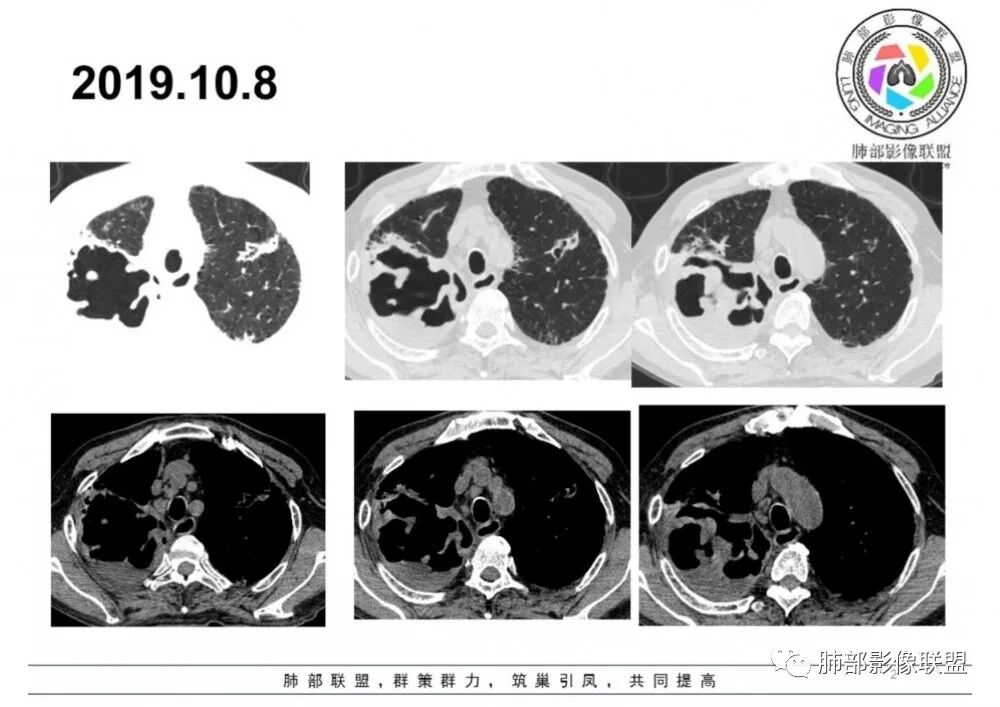

1.老年男性患者,间断发热、咳嗽、乏力月余。注意这病史不算长,症状相对轻,没有咯血。

2.双肺多发病灶,主要集中在右肺,斑片影、结节影,条索影,支扩等等,右肺病灶胸膜下居多,密度偏高不均,偶见钙化。

3.右肺巨大空洞影。值得注意的是:

1.肺结核的诊断是符合的,或者说是存在的。

2.应考虑伴细菌感染,尤其是G-杆菌感染。

患者病程相对短,出现高热,空洞内液平都提示这种可能,何况肺部其他一些边界不清的渗出病灶。